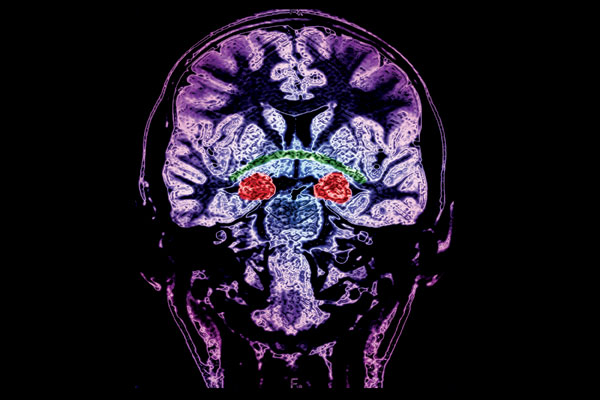

When the brain learns something—a new skill or a fear response, for example—neurons gain surface receptors at synaptic connections that strengthen signals from neighboring neurons. When fear is learned, this strengthening happens in an area of the brain known as the lateral amygdala.

The researchers examined the animals' brains at various times postshock. After a few hours, the number of glutamate receptors—common in neuron signaling—had increased at synapses in the lateral amygdala. Twenty-four hours later though, most of these receptors had lost a subunit, turning them into more rare calcium-penetrable AMPA receptors (CP-AMPARs). This finding was a surprise, especially since, a few days later, the receptors regained the subunit, returning to the more common form.